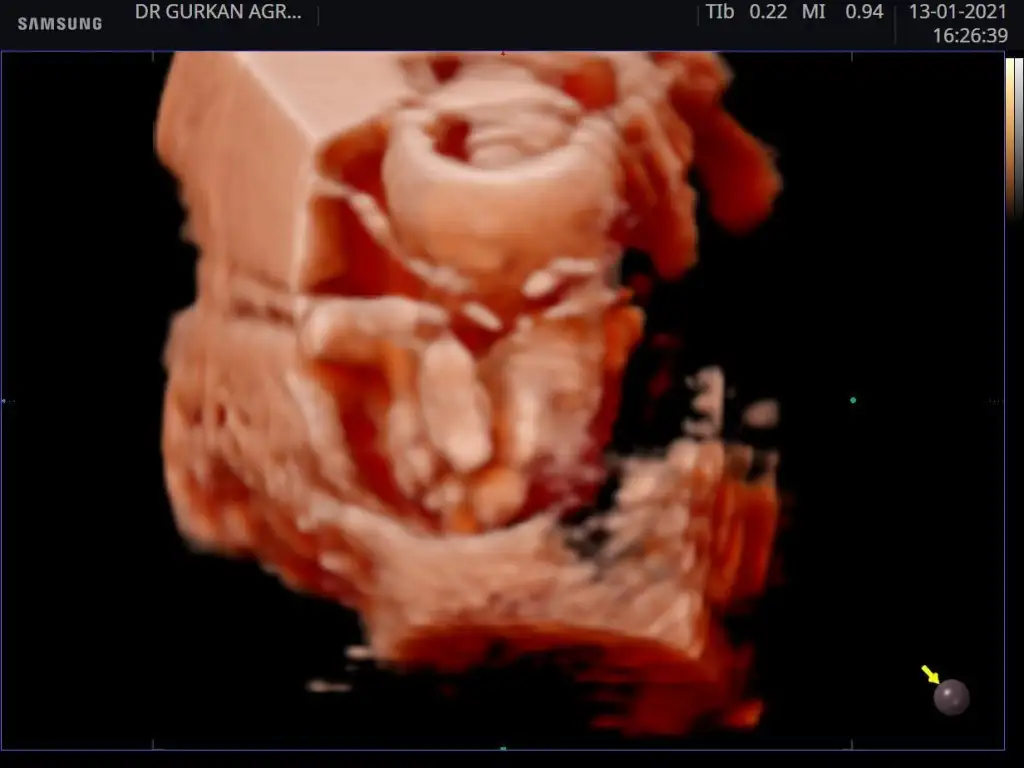

Hayirli sağlıklı olsun.dr mu soyledi.usg paylasmistin degil mi burada.gelecegi parlak cok sansli olsun bebegin.Benim ki. Kız kesin

Evet Dr söyledi teşekkürlerHayirli sağlıklı olsun.dr mu soyledi.usg paylasmistin degil mi burada.gelecegi parlak cok sansli olsun bebegin.

Ben de kız demistim .o haftalik ultrason kaginda daha belli oluyor cinciyet tahmini.çıkınti paralel oldugu icin kız demistim ben de.buradaki fotoda net belli sizin.seni çok iyi anlıyorum.benim de iki kızım var.ve ücuncuyu istiyoruz.olmadi 5 aydir gebelik.hayırlısı olsun.saglikli olsun en önemlisi.Rabbimin vardır bildiği .verdiyse en hayırlısını vermistir.gönlünü ferah tut .Evet Dr söyledi teşekkürlerEki Görüntüle 2764435

Ama çoğu kişi erkek bu bebek diyorBen de kız demistim .o haftalik ultrason kaginda daha belli oluyor cinciyet tahmini.çıkınti paralel oldugu icin kız demistim ben de.buradaki fotoda net belli sizin.seni çok iyi anlıyorum.benim de iki kızım var.ve ücuncuyu istiyoruz.olmadi 5 aydir gebelik.hayırlısı olsun.saglikli olsun en önemlisi.Rabbimin vardır bildiği .verdiyse en hayırlısını vermistir.gönlünü ferah tut .